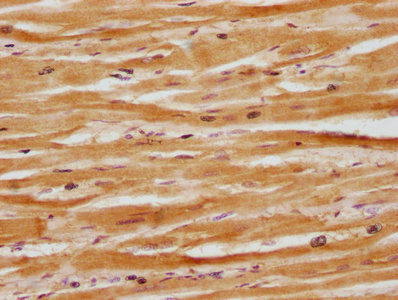

IHC image of CSB-PA839833LA01HU diluted at 1:100 and staining in paraffin-embedded human heart tissue performed on a Leica BondTM system. After dewaxing and hydration, antigen retrieval was mediated by high pressure in a citrate buffer (pH 6.0). Section was blocked with 10% normal goat serum 30min at RT. Then primary antibody (1% BSA) was incubated at 4°C overnight. The primary is detected by a biotinylated secondary antibody and visualized using an HRP conjugated SP system.